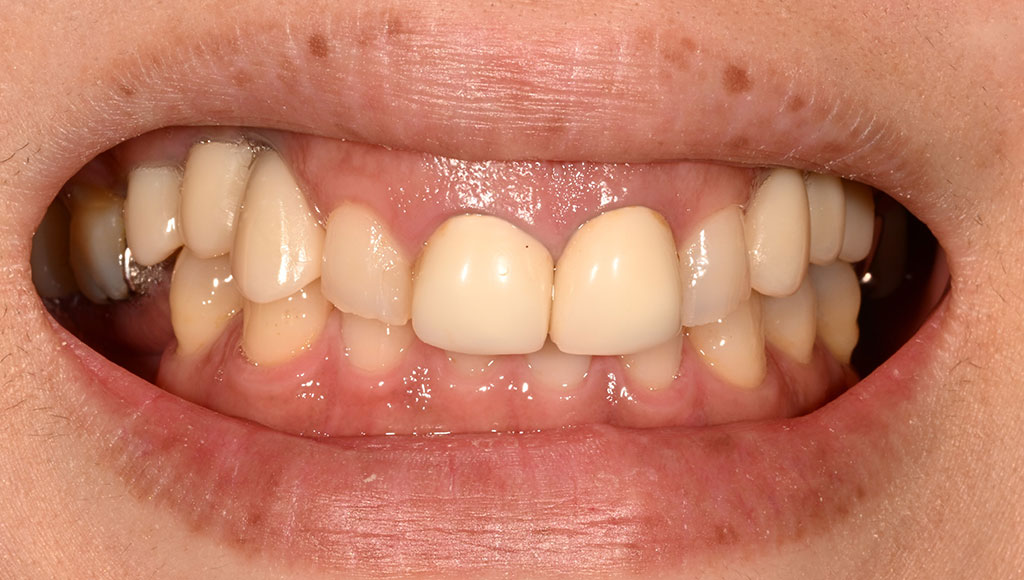

Before2

患者様の主訴

40代女性。横浜市在住。左上1番右上1番のクラウンに着色があり審美的に問題を抱えていたため、ご来院されました。

診断結果

ジルコニアクラウンを装着するために元のブリッジを外し、歯の形成を行いジルコニアクラウンをセット

治療内容

ジルコニアクラウンを装着するために元のクラウンを外し、歯の形成を行い光学印象(プライムスキャンによる)型取りを行いました。光学印象のデータを元に当院の院内技工室にてデジタル加工を行い、ジルコニアクラウンを作成し、セットを行いました。

治療期間

2回

治療費用

総額:330,000円(税込)

◼️内訳

ジルコニアクラウン(前歯):150,000円(税込)/1本×2本

光学印象(プライムスキャン)

リスク・副作用

補綴物の脱落・欠落、咬合違和感、色調補正